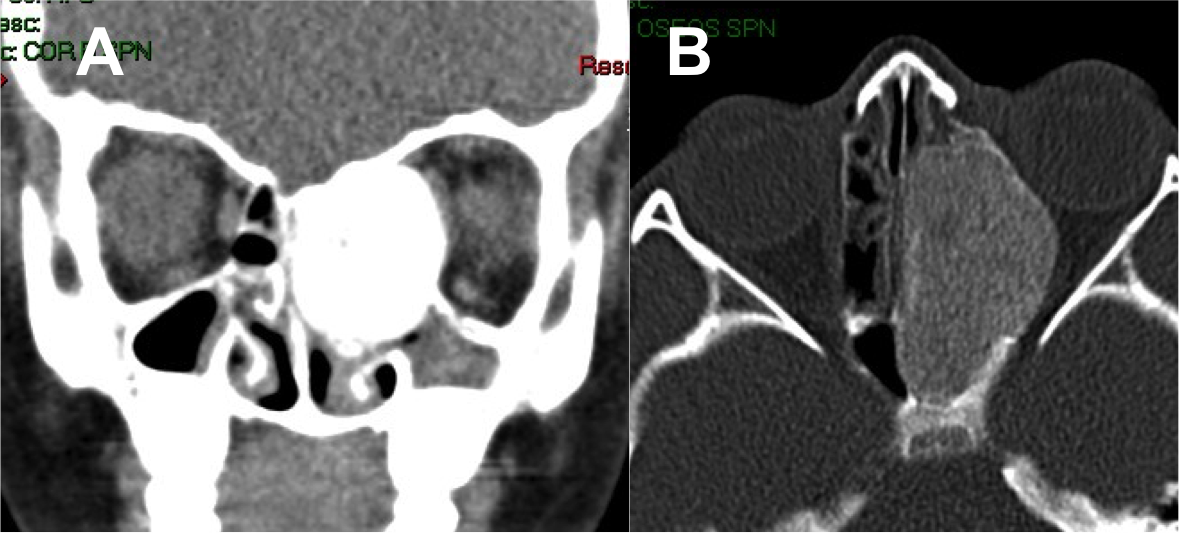

Introducción: La cirugía endoscópica endonasal se ha convertido en una herramienta fundamental para el manejo de patologías que comprometen la base de cráneo. En casos bien seleccionados, estas técnicas permiten resecciones quirúrgicas con una menor morbilidad sin comprometer los principios oncológicos de resección. Con el desarrollo de instrumental especializado, nuevas tecnologías y la experiencia de los cirujanos, la cirugía endoscópica endonasal se usa cada vez más en cirugía de base de cráneo en niños.

Diseño: Estudio observacional descriptivo de tipo serie de casos. Metodología: se describe la experiencia con pacientes pediátricos llevados a cirugía endoscópica endonasal para manejo de tumores de base de cráneo en el Instituto Nacional de Cancerología entre julio de 2014 y diciembre de 2016.

Resultados: Fueron intervenidos 8 pacientes entre los 2 y 14 años, con una edad promedio de nueve años y un seguimiento promedio de 16 meses. En el 75% se hizo una resección total del tumor. Un paciente requirió una reintervención y un paciente fue sometido a radiocirugía post-operatoria. 1 paciente falleció a pesar de múltiples intervenciones, quimioterapia y radioterapia.

Conclusión: La cirugía endoscópica endonasal para tumores de base de cráneo puede ser utilizada de forma segura en los pacientes pediátricos, es una técnica que en casos bien seleccionados pueden ofrecer excelentes resultados disminuyendo la morbilidad y complicaciones de las técnicas abiertas.